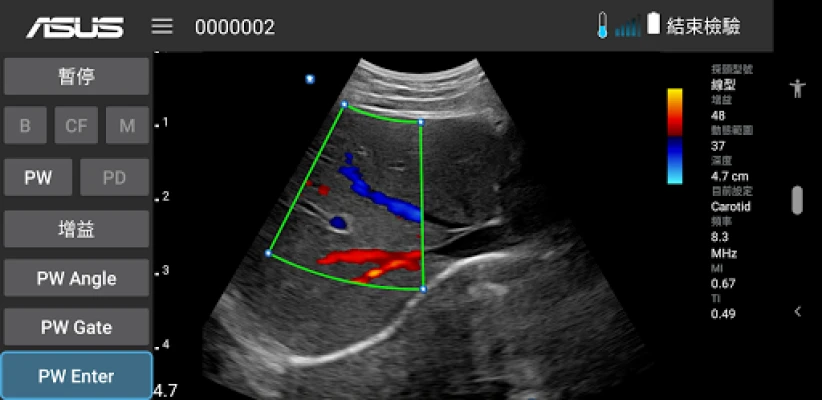

ASUS Portable Ultrasound is a wireless, handheld, pocket-sized imaging tool.

This flexible and feasible APP supports reliable and dependable images for diverse scenarios.